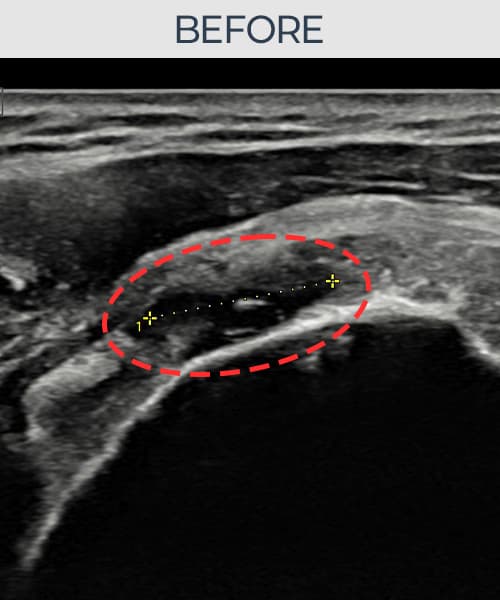

超声确认旋转肌腱袖 关节面侧部分撕裂(14mm × 7mm (肌腱厚度约68%缺损))。缩小缝合术后肌腱连续性恢复,患者回归正常生活。

术前

术前超声确认旋转肌腱袖 关节面侧部分撕裂,冈上肌腱回声不连续伴肌腱缺损(14mm × 7mm (肌腱厚度约68%缺损))。术后超声显示撕裂部位充满再生组织,肌腱连续性恢复,回声模式正常化。

该患者持续肩痛。详细超声检查确认旋转肌腱袖 关节面侧部分撕裂(缺损:14mm × 7mm (肌腱厚度约68%缺损))。在超声引导下实施非手术缩小缝合术。术后佩戴支具约4-6周,随后进行分阶段康复锻炼。随访超声确认肌腱连续性恢复、结构稳定,患者顺利回归日常生活。